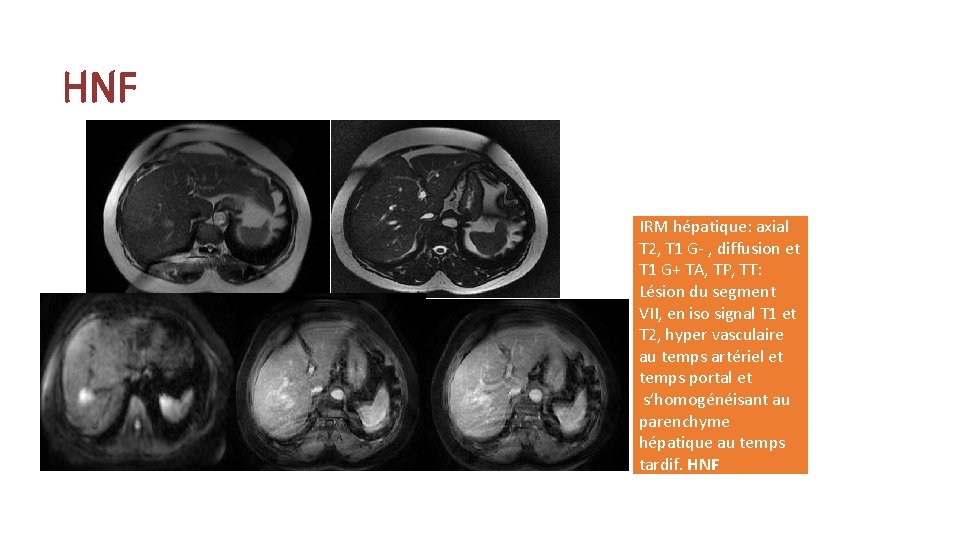

HNF IRM hépatique: axial T 2, T 1 G- , diffusion et T 1 G+ TA, TP, TT: Lésion du segment VII, en iso signal T 1 et T 2, hyper vasculaire au temps artériel et temps portal et s’homogénéisant au parenchyme hépatique au temps tardif. HNF

Bénignes : Hyperplasie nodulaire focale: • La seconde tumeur bénigne par ordre de fréquence après l’hémangiome, souvent de découverte fortuite. • Quasiment toujours asymptomatique et toujours bénigne. • Echographie: Iso-échogène, hypoéchogène ou hyperéchogène de contours lobulés, ayant une cicatrice centrale. • Scanner: • Sur l’acquisition non injectée iso-dense ou hypodense. • Sur les acquisitions injectées: au temps artériel prise de contraste intense sauf la zone centrale, aux temps portal et tardif elle redevient iso-dense au parenchyme hépatique avec l’élément central qui se rehausse au temps tardif.